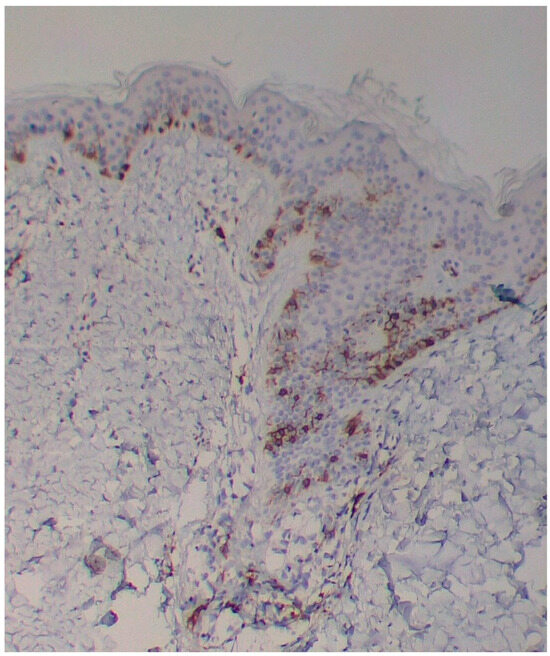

A skin biopsy showed basal cell hyperpigmentation and a chronic superficial perivascular inflammatory infiltrate that also affected the periphery of the hair follicles (Figure 6). Tryptase stain reached figures of up to 29 mast cells per high-power view (67/mm2), and CD117 up to 46 mast cells per high-power view (92/mm2), mostly surrounding the hair infundibulum (Figure 7), although some interstitial mast cells were also observed (Figure 8). PAS stain was negative for yeasts or fungal hyphae. Abdominal ultrasound study did not detect any anomalies. The bone scintigram detected mild non-specific osteoblastic lesions in the L5, S1 and sacroiliac joints (pending further study).

Figure 7. Mast cell infiltration in superficial dermis and around a pilosebaceous follicle (CD117 ×100).